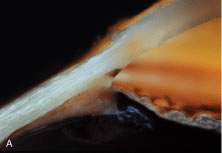

Aqueous humor is a clear nutrient fluid, derived from plasma, that provides for the metabolic needs of the avascular tissues of the eye. Although free amino acid levels in aqueous humor are nearly equivalent to those found in plasma,14 the protein content of aqueous humor in the anterior chamber is less than 1% of that found in plasma.15 Proteins create turbidity and turbidity scatters light, which degrades the optical efficiency of the eye. To prevent this and to ensure that potential antigens in the bloodstream are prevented from reaching the anterior and posterior chambers of the eye and the lens, vitreous, and retina, a selective barrier must be positioned between the bloodstream and the aqueous humor. As noted earlier, the microvasculature of the ciliary body stroma is composed of fenestrated capillaries that readily leak fluids, ions, and plasma proteins to provide the reservoir from which the ciliary epithelium secretes aqueous humor. To ensure that the protein-laden fluid in the ciliary body stroma and the composition of the aqueous humor remain different, a barrier to macromolecular diffusion is interposed between the ciliary body stroma and the posterior chamber by the ciliary epithelium.16 As noted earlier (see Figs. 8 to 10), following injection of HRP in monkeys, this protein readily leaves the lumen of the fenestrated capillaries of the ciliary body stroma.17 The protein diffuses to the ciliary epithelium and easily moves between adjacent pigmented ciliary epithelial cells, filling the intercellular cleft18 (Fig. 14A). On reaching the interface between the juxtaposed apical surfaces of the pigmented and nonpigmented layers, the HRP is again able to freely permeate the intercellular cleft between these cell layers. But when the HRP attempts to diffuse along the intercellular cleft between adjacent nonpigmented ciliary epithelial cells, its progress toward the aqueous humor in the posterior chamber is blocked by an apicolateral junctional complex composed of a zonula occludens (tight junction), a zonula adherens, and desmosome19,20 (see Fig. 14A). In sections, the tight junction is seen as a series of apparent fusion points between the membranes of adjacent nonpigmented ciliary epithelial cells (see Fig. 14,Inset). Using the technique of freeze-fracture, however, allows an en face view of the tight junctions, revealing that these fusion points are actually cross sections of a complex system of branching and anastomosing protein strands that surround the entire circumference of each cell.19 This web of strands spans the intercellular cleft and is mirrored on the adjacent cell, which blocks the intercellular cleft around the entire circumference of each cell, to limit diffusion of macromolecules (see Fig. 14B). Disruption of this junctional complex has been shown to occur in experimental anterior uveitis, resulting in increased amounts of protein in the aqueous humor.21 This extra protein scatters the light of the slit lamp and is described clinically as flare.

Fig. 14. A. Black horseradish peroxidase (HRP) reaction product fills the ciliary body stroma (asterisk) and blackens the intercellular cleft between adjacent pigmented ciliary epithelial cells, as well as the cleft between the apical surfaces of the pigmented and nonpigmented layers. Further diffusion of HRP toward the posterior chamber is blocked by tight junctions between adjacent nonpigmented epithelial cells (arrowheads). Inset. Higher magnification demonstrates the points of fusion (arrows) between membranes of adjacent nonpigmented ciliary epithelial cells that constitute the tight junction. B. Freeze-fracture electron micrograph demonstrates the branching and anastomosing tight junctional strands of a zonula occludens between adjacent nonpigmented ciliary epithelial cells. (From Morrison JC, Van Buskirk EM, Freddo T. Anatomy, microcirculation and ultrastructure of the ciliary body. In: Ritch R, Shields MB, Krupin T (eds). The Glaucomas. St Louis: CV Mosby, 1989.)